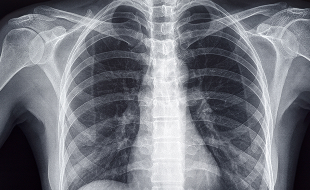

• 胸部X線検査(レントゲン)

肺や胸部の異常を調べる基本的な検査です。短時間で負担が少なく、多くの呼吸器疾患の初期診断に用いられます。